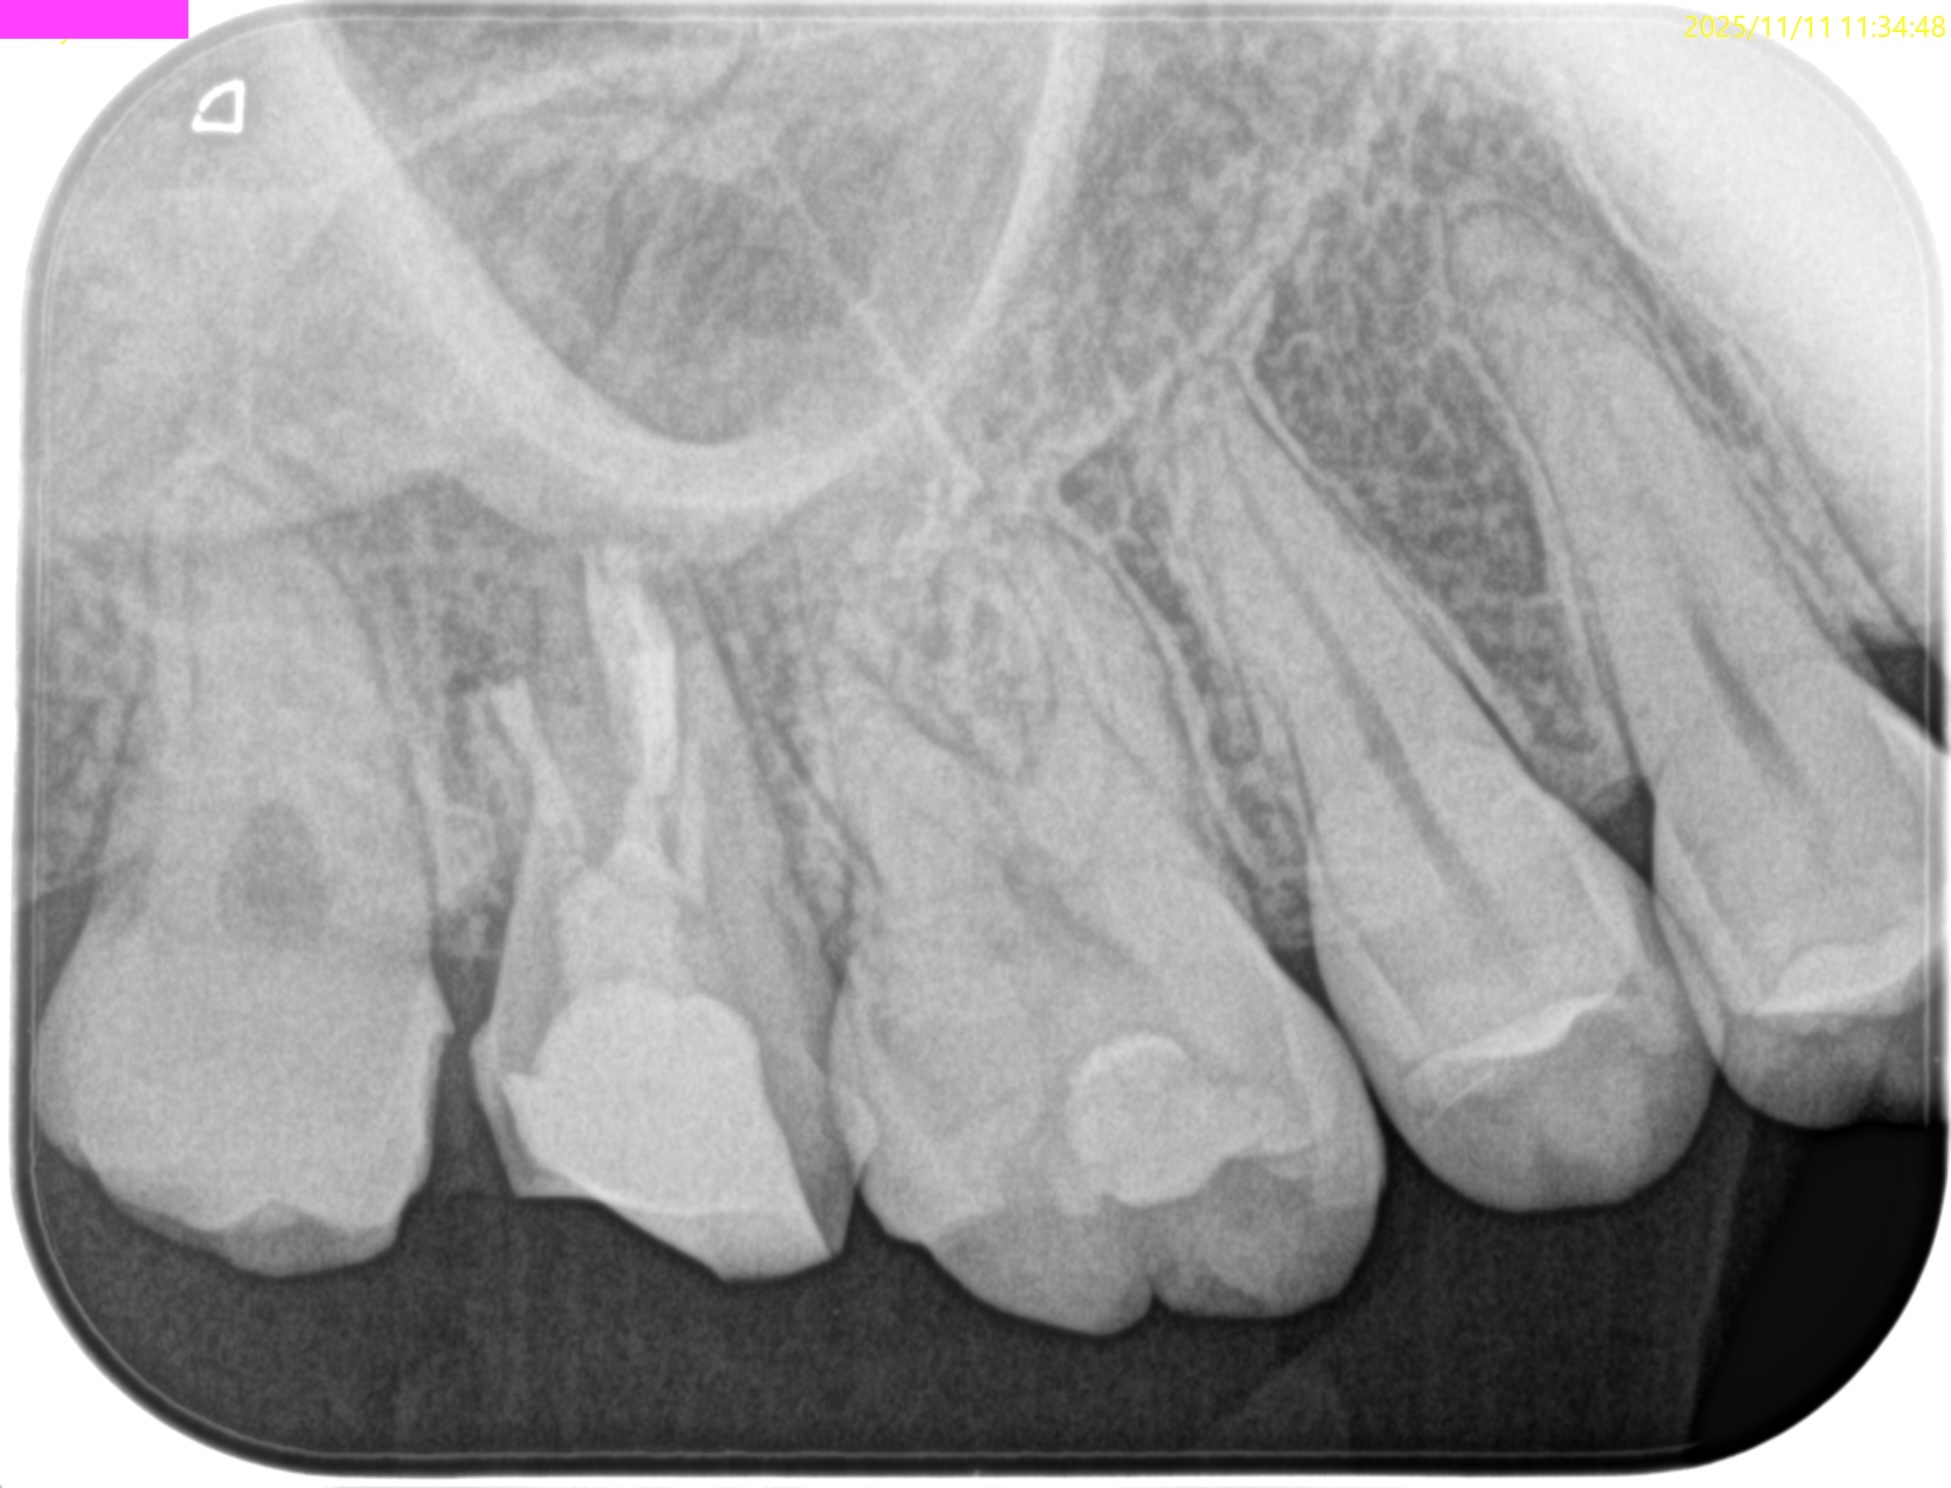

術後にPAを撮影した。

MB

DB

P

B

問題はないだろう。

逆根管充填の状態をイマイチ智度確認した。

MBをもう少し頬側方向に逆根管形成を広げた方がいいのだろうか?と疑問を持ったからだ。

が、

メチレンブルーが染まった場所を私は信じることにした。

この後、口腔外で除冠し、築造した。

その状態で抜歯窩に戻している。

術後にPA, CBCTを撮影した。